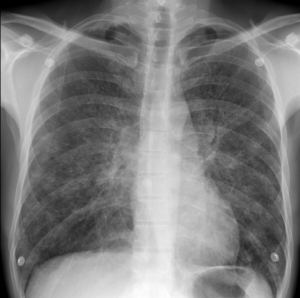

Виды рентгена при пневмонии у детей

Рентген — это современный способ диагностики многих респираторных заболеваний. Часто это важно при диагностике пневмонии у детей. Современные медицинские клиники используют рентген для определения типа и стадии воспаления в легких, что дает возможность назначить более точное и эффективное лечение. Во многих случаях можно обойтись без рентгена. Например, при безобидной экологической пневмонии не всегда целесообразно подтверждать …